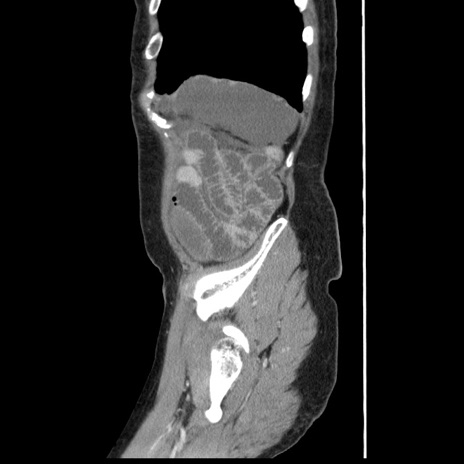

横断像

【症例】80歳代女性

【主訴】腹痛

【現病歴】8時間前から腹痛あり来院。

【既往歴】糖尿病、脂質異常症、子宮体癌にて子宮全摘術

【身体所見】意識清明・会話良好だが腹痛で苦悶様、全腹部にわたって反跳痛と圧痛あり

【データ】WBC 13600、CRP 0.14、LDH 224、CK 90